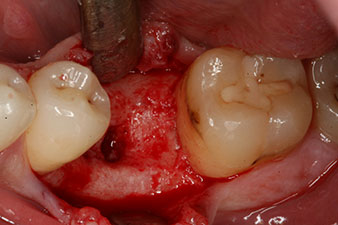

No obstante, seis semanas después de la extracción, tras la disección del colgajo mucoperióstico, se observó una osificación incompleta en el área del antiguo alvéolo mesial.

Tras la extirpación minuciosa del tejido de granulación, se incorporó el implante tal como se había planificado (blueSky, bredent).

El torque en el momento de la carga mecánica fue de 43 Ncm. Asimismo, después de atornillar un poste de medición especial adaptado al sistema de implante (SmartPeg), el valor ISQ se determinó con la sonda del módulo Osstell ISQ de W&H.

Este habría permitido una cicatrización abierta o incluso un tratamiento inmediato. Sin embargo, como no se disponía de suficiente hueso en la parte crestal del implante, el área se aumentó con las virutas óseas recopiladas durante la preparación del lecho del implante y se suturó para que no penetrara saliva.